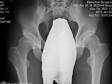

Мне 30 лет. С 6 лет занимаюсь футболом. Год назад сделал снимок тазобедренного сустава (прилагается) поставили диагноз диспластический кокартроз 1ст., после продолжил активные занятие футболом никаких болей не испытывал. С августа месяца прекратил занятие спортом стали появляться неприятные ощущения в области сустава (особенно в положении сидя) но болевых ощущений нет движения не ограничены.